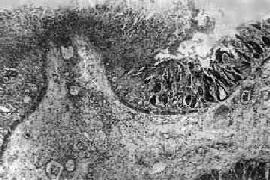

图18-22 细菌性痢疾 结肠粘膜表层坏死并有白细胞和纤维素性渗出物

第四节 细菌性痢疾细菌性痢疾(bacillary dysentery)是痢疾杆菌引起的一种常见肠道传染病。全年均可发生,但以夏秋季为多见。儿童发病率一般较高,其次是20~39岁青壮年,老年患者较少。 【病因及传染途径】 痢疾杆菌是革兰染色阴性的短杆菌。按抗原结构和生化反应可分为四群。福氏菌(Shigella flexneri)、宋内氏菌(Sh.sonnei)、鲍氏菌(Sh.boydii)和志贺氏菌(Sh.dysenteriae)。所有痢疾杆菌均能形成内毒素,志贺氏菌除内毒素外,还可产生外毒素。现用Ipa质粒抗原和志贺毒素(ShT)基因作PCR测定,为快速诊断开辟了新的徐径。 菌痢患者和带菌者是本病的传染源。痢疾杆菌从粪便中排出后,可直接或间接(通过苍蝇等)污染食物、饮水、食具、日常生活用具和手等,再经口传染给健康人。食物和饮水的污染有时可引起菌的暴发流行。 【发病机制】 痢疾杆菌经口进入消化道后,在抵抗力较强的健康人可被胃酸大部分杀灭,即使有少量未被杀灭的病菌进入肠道,亦可通过正常肠道菌群的拮抗作用将其排斥。此外,在有些过去曾受感染或隐性感染的患者,其肠粘膜表面有对抗痢疾杆菌和特异性抗体(多属分泌性IgA),能排斥痢疾杆菌,使之不能吸附于肠粘膜表面,从而防止菌痢的发生。而当人体全身及局部抵抗力降低时,如一些慢性病、过度疲劳、暴饮暴食及消化道疾患等,即使感染小量病菌也容易发病。 痢疾杆菌侵入肠粘膜上皮细胞后,先在上皮细胞内繁殖,然后通过基底膜侵入粘膜固有层,并在该处进一步繁殖,在其产生的毒素作用下,迅速引起炎性反应,其强度与固有层中的细菌数量成正比,肠上皮细胞坏死,形成溃疡。菌体内毒素吸收入血,引起全身毒血症。 中毒型菌痢大多发生于儿童,其发病机制尚未查明,可能因患者为特异体质,故对细菌毒素呈强烈过敏反应。 【病理变化及临床病理联系】 菌痢的病理变化主要发生于大肠,尤以乙状结肠和直肠为重。病变严重者,整个结肠甚至回肠下段也可受累。根据肠道炎症特征、全身变化和临床经过的不同,菌痢可分为以下三种: 1.急性细菌性痢疾 病变初期呈急性卡他性炎,表现为粘液分泌亢进,粘膜充血、水肿、点状出血、中性粒细胞及巨噬细胞浸润,粘膜上皮坏死脱落后形成表浅糜烂。粘膜下层也可见炎性反应,但程度较轻。病变进一步发展乃成为本病特征性的假膜性炎,表现为粘膜表层坏死,同时在渗出物中出现大量纤维素,后者与坏死组织、中性粒细胞、红细胞和细菌一起形成假膜(图18-22)。假膜首先出现于粘膜皱襞的顶部,呈糠皮状,随着病变扩展可融合成片。假膜一般呈灰白色,如出血严重或被胆色素浸染时,则可分别呈暗红色或灰绿色(图18-23)。大约在发病后一周左右,在中性粒细胞破坏后释出的蛋白溶解酶作用下,纤维素和坏死组织发生溶解液化,而使假膜成片脱落,形成大小不等、形状不一的溃疡。溃疡多数浅表,甚少穿破粘膜肌层,但亦偶有深达肌层引起穿孔导致腹膜炎者。当病变趋向愈复时,肠粘膜的渗出物和坏死物逐渐被吸收、排出,组织的缺损经再生而修复。浅小的溃疡愈合后无明显瘢痕形成,深而较大的溃疡愈合后可形成浅表瘢痕,很少引起肠腔狭窄。